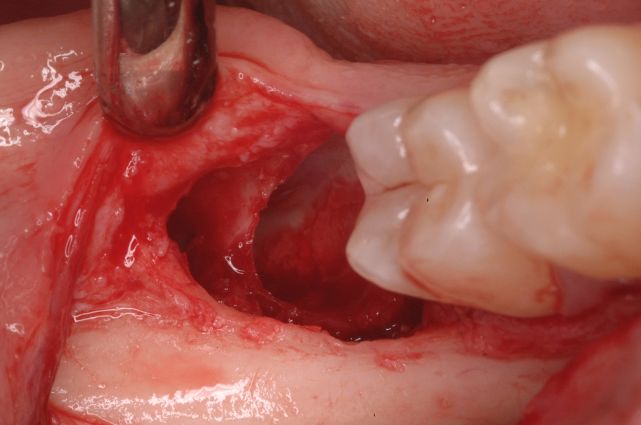

Dovrebbe essere determinato il grado di difficoltà, sulla base di una serie di fattori quali la classificazione radiografica di inclusione proposta da Pell e Gregory (15), la configurazione radicolare, il grado di apertura della bocca, il riflesso del vomito e l’età del paziente. L’ultimo passo prima dell’intervento è quello di ricevere il consenso informato del paziente. Il capitolo dedicato al trattamento chirurgico presenta due casi clinici di terzi molari inferiori inclusi in posizione orizzontale e mostra la tecnica, passo dopo passo, dall’incisione di un lembo mucoperiosteo all’utilizzo dell’approccio vestibolare e l’utilizzo delle frese per eseguire la rimozione ossea e il sezionamento del dente.

Quando viene applicata una tecnica chirurgica efficace, il successo del trattamento diventa un risultato predicibile e diminuirà l’incidenza delle complicanze intra- e postoperatorie quali l’infezione secondaria, l’eccessivo sanguinamento intra- e postoperatorio, l’edema, l’ecchimosi, l’ematoma, l’alveolite postestrattiva, il trisma, il dolore postoperatorio, i traumi ai tessuti molli e all’articolazione temporo-mandibolare, la lesione del nervo alveolare inferiore e del nervo linguale, la frattura mandibolare, la rottura di strumenti e la loro possibile ingestione da parte del paziente, i danni parodontali o restaurativi a carico del secondo molare, l’enfisema, la frattura del tavolato corticale linguale e la dislocazione del dente o delle radici negli spazi anatomici adiacenti.

Lower third molar extraction is one of the most common intervention in minor oral surgery. Indications for removal are pericoronitis, cysts and tumours, lack of space, second molar impaction, malposition, caries, periodontitis, restorative or prosthetic treatments, pathologic resorption, idiopathic symptoms, and orthodontic needs. Presurgical evaluation includes medical history, clinical and radiographic examination, based on panoramic and periapical films, and computed tomography when needed. Surgical risk should be evaluated according to Pell & Gregory radiological scale, root shape, mouth opening extension, vomit’s reflex and patients’ age. Informed consent is also necessary before surgery. Two cases are reported showing a step by step buccal approach by a mucoperiosteal flap and teeth splitting. When an effective surgical technique is used, clinical success becomes a predictable result; at the same time, it reduces both surgical and post-surgical complications, such as secondary infection, excessive bleeding, swelling, alveolitis, trismus, pain, soft tissues and temporomandibular joint trauma, mandible fracture, broken instruments and their ingestion, second molar periodontal and restorative damages, emphysema, lingual plate fracture, and displacement of teeth or roots in the adjacent spaces.